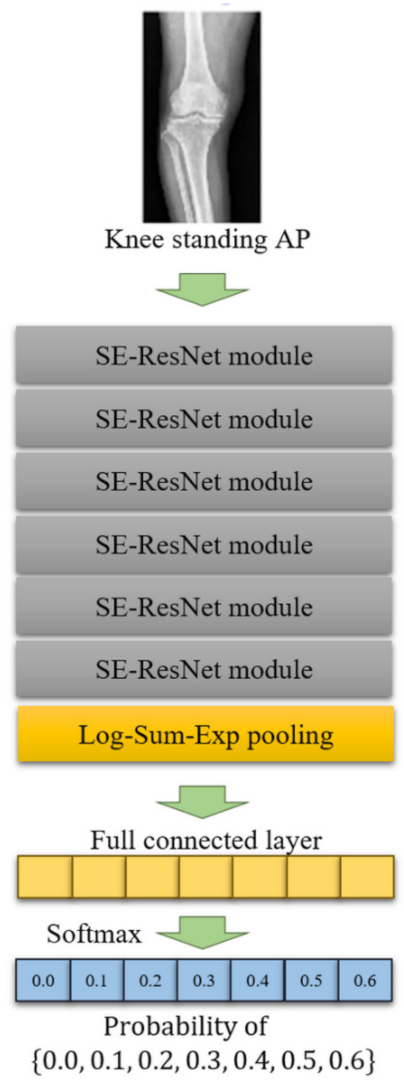

2.4. DL Algorithm